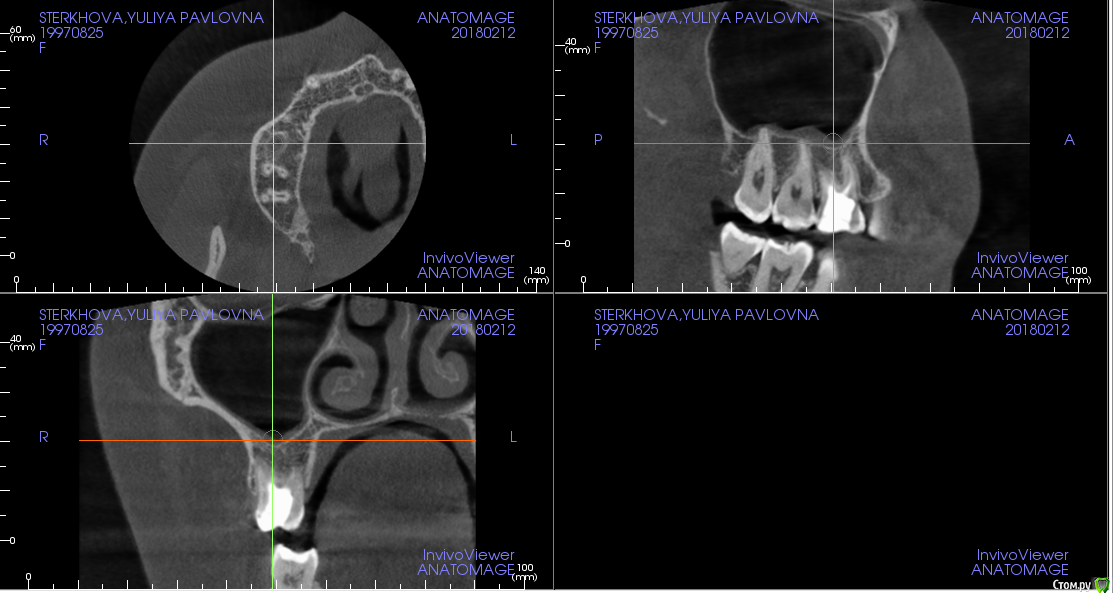

Стерхова Юлия Опубликовано 1 марта, 2018 Автор Поделиться Опубликовано 1 марта, 2018 (изменено) Снова здравствуйте! Так зуб и не хочет оставить меня в покое. С момента последнего сообщения был сделан 3д снимок (прилагаю ссылку с ним на файлообменник: https://ru.files.fm/u/u275ad6j),на котором врач нашёл недепульпированный 4 канал. Неделю назад этот канал прочистили (оказался пустым), поставили временную пломбу, но боль не исчезла, только усилилась. На следующем приеме врач сделал прицельный снимок и нашёл незапломбированный до конца третий канал, а также хроническое воспаление. Было принято решение перелечить все оставшиеся три канала, чтобы не допустить повторения воспалительного процесса. При этом даже через двойную дозу анестезии я чувствовала при лечении сильнейшую боль. Так же была по итогу поставлена временная пломба, выписали антибиотик и обезболивающее. Прошло двое суток после лечения, сильная боль во всем зубе продолжает беспокоить - сильней во много раз, чем до лечения. Нормально ли это? Или все-таки даже и это лечение не помогает? Возможно ли, что дело дойдет до удаления? Изменено 1 марта, 2018 пользователем Стерхова Юлия Ссылка на комментарий

Стерхова Юлия Опубликовано 1 апреля, 2018 Автор Поделиться Опубликовано 1 апреля, 2018 Выкладываю старые срезы с опозданием(Я уже не знаю, как быть. Подскажите, пожалуйста! В общем, каналы уже месяц перелечиваются под микроскопом, диагноз - периодонтит. Примерно каждую неделю все прочищается и закладывается под временную пломбу лекарство, но результата нет - сохраняется боль в ночное время и во время очищения каналов. В гайморовой гранулёма. Несмотря на все это, хирург выступает категорически против удаления, терапевт тоже, на 7.04 запланирована пломбировка. Но на этой неделе я обратилась к ЛОРу, он поставил диагноз тонзиллит (на фоне инфицирования зуба), гайморит (из-за гранулёмы), а также нашел остаток пломбировочного материала в пазухе. Он - за удаление. Хирург наличие пломбы в пазухе отрицает. Кому верить в данной ситуации? Когда лучше сделать новое КТ: до или после пломбировки? И стоит ли пломбировать? Своим врачам я доверяю, но ЛОР заставил меня засомневаться, как и сохранение болей( Ссылка на комментарий

Стерхова Юлия Опубликовано 3 апреля, 2018 Автор Поделиться Опубликовано 3 апреля, 2018 Вот новые срезы КТ, сделанного вчера. Интересует белый кончик у канала (первый скриншот) - это резорбция? Ссылка на комментарий